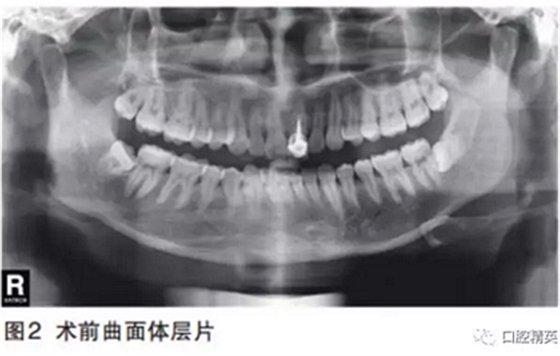

曲面體層片示21已行根管治療并樁冠修復(fù)。牙周膜正常,根尖無暗影,遠(yuǎn)中牙槽嵴頂骨質(zhì)略吸收1mm。

印象診斷:21根折。